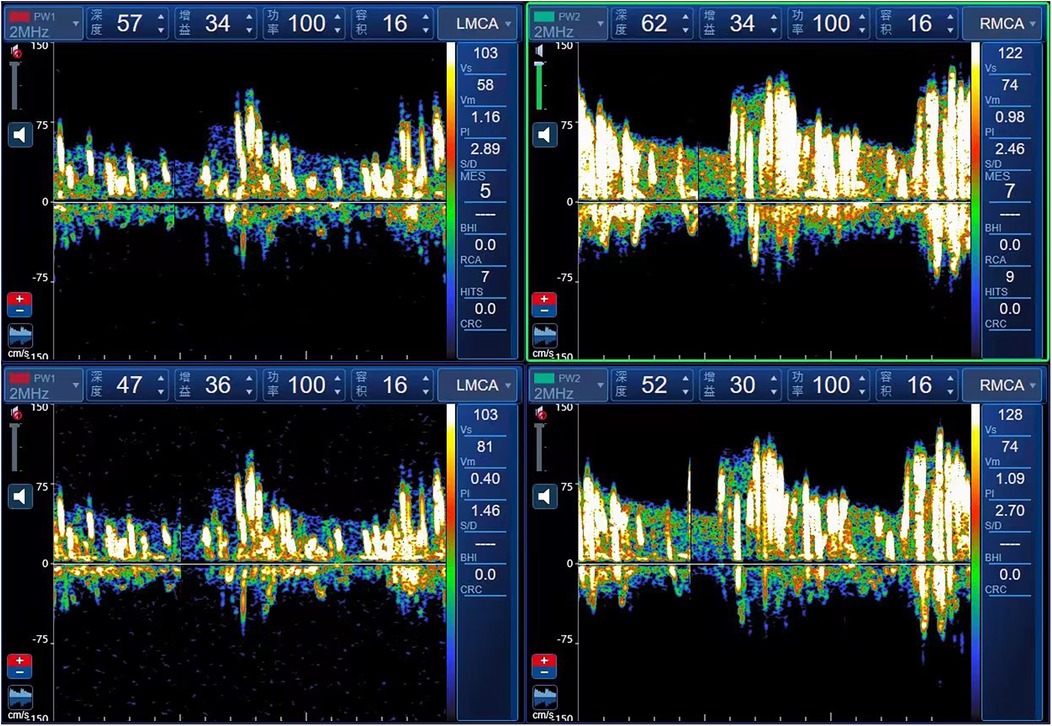

The c-TCD grading standard follows the 2,000 guidelines for detecting right-to-left shunt using an ultrasound contrast agent and transcranial Doppler sonography (10). The intervention procedure involved injecting a microvesicle contrast agent (a mixture of 9 ml saline and 1 ml air) through the elbow vein and insonating at least one middle cerebral artery (MCA) using TCD. If a right-to-left shunt is present, microbubbles can enter the left heart and systemic circulation through an abnormal pathway. Microbubbles signals entering the cerebral arteries can be monitored by TCD and are more easily detected during the Valsalva manoeuvre. If no microbubbles are detected at rest, the Valsalva manoeuvre (10 s duration, initiated 5 s post-injection) is repeated. According to the number of microbubbles, shunts are categorised into four grades: Grade 0, no microbubbles detected; Grade Ⅰ, 1–10 microbubbles; Grade Ⅱ, >10 microbubbles without a curtain effect; and Grade Ⅲ, embolic signal curtain or shower type. Children diagnosed with PFO and migraine were screened and referred to the Ultrasound Department for further examination. The grade III c-TCD foaming test is illustrated in Figure 1.